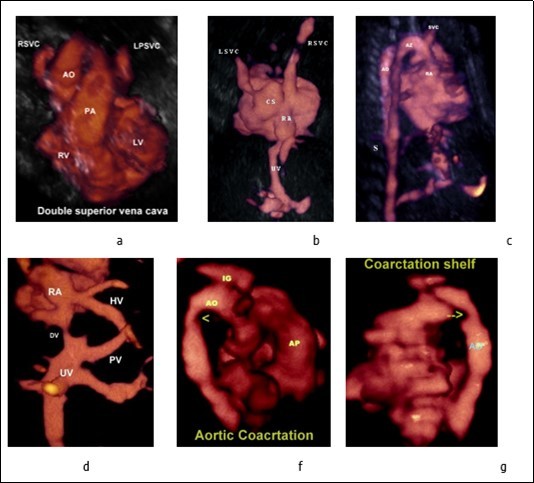

Figure 4.a-Three-vessel-trachea view showing the persistent left superior vena cava located left of the pulmonary artery. b-Persistent left superior vena cava draining into the dilated coronary sinus and to the right atrium, the coronary sinus is aneurysmal. c-Three-dimensional ultrasound in glass body mode showing the Azygos vein and Aorta. d- Anomalous hepatic venous drainage directly into the right atrium. e, f- Aortic coarctation (arrow head), note the presence of coarctation shelf (arrow). Abbreviations: RA: right atrium AO: aorte UV: umbilical vein AP : Pilmonary artery PV: Portal vein DV : Ductud venosus

Bilateral superior vena cava (SVC) occurs in about 41 % of cases of left atrial Isomerism and in 36 % cases of asplenia or right atrial Isomerism. 11 A (PLSVC) was diagnosed in two patients, with 3D ultrasound and Doppler, we have been able to reconstruct the 3D anatomy of the persistent left superior vena cava draining into the dilated coronary sinus and to the right atrium (Figure 4 b); moreover, reconstructing the 3-vessel view, a fourth vessel (PLSVC) is seen on the left side of the pulmonary artery. (Figure 4 a).). In left atrial isomerism, multiple spleens, from 2 to 16, can be found, usually along the greater curvature of the stomach. 12. Anomalies of midgut derivatives include nonrotation, incomplete rotation, and the rare reversed complete or incomplete rotation. 30